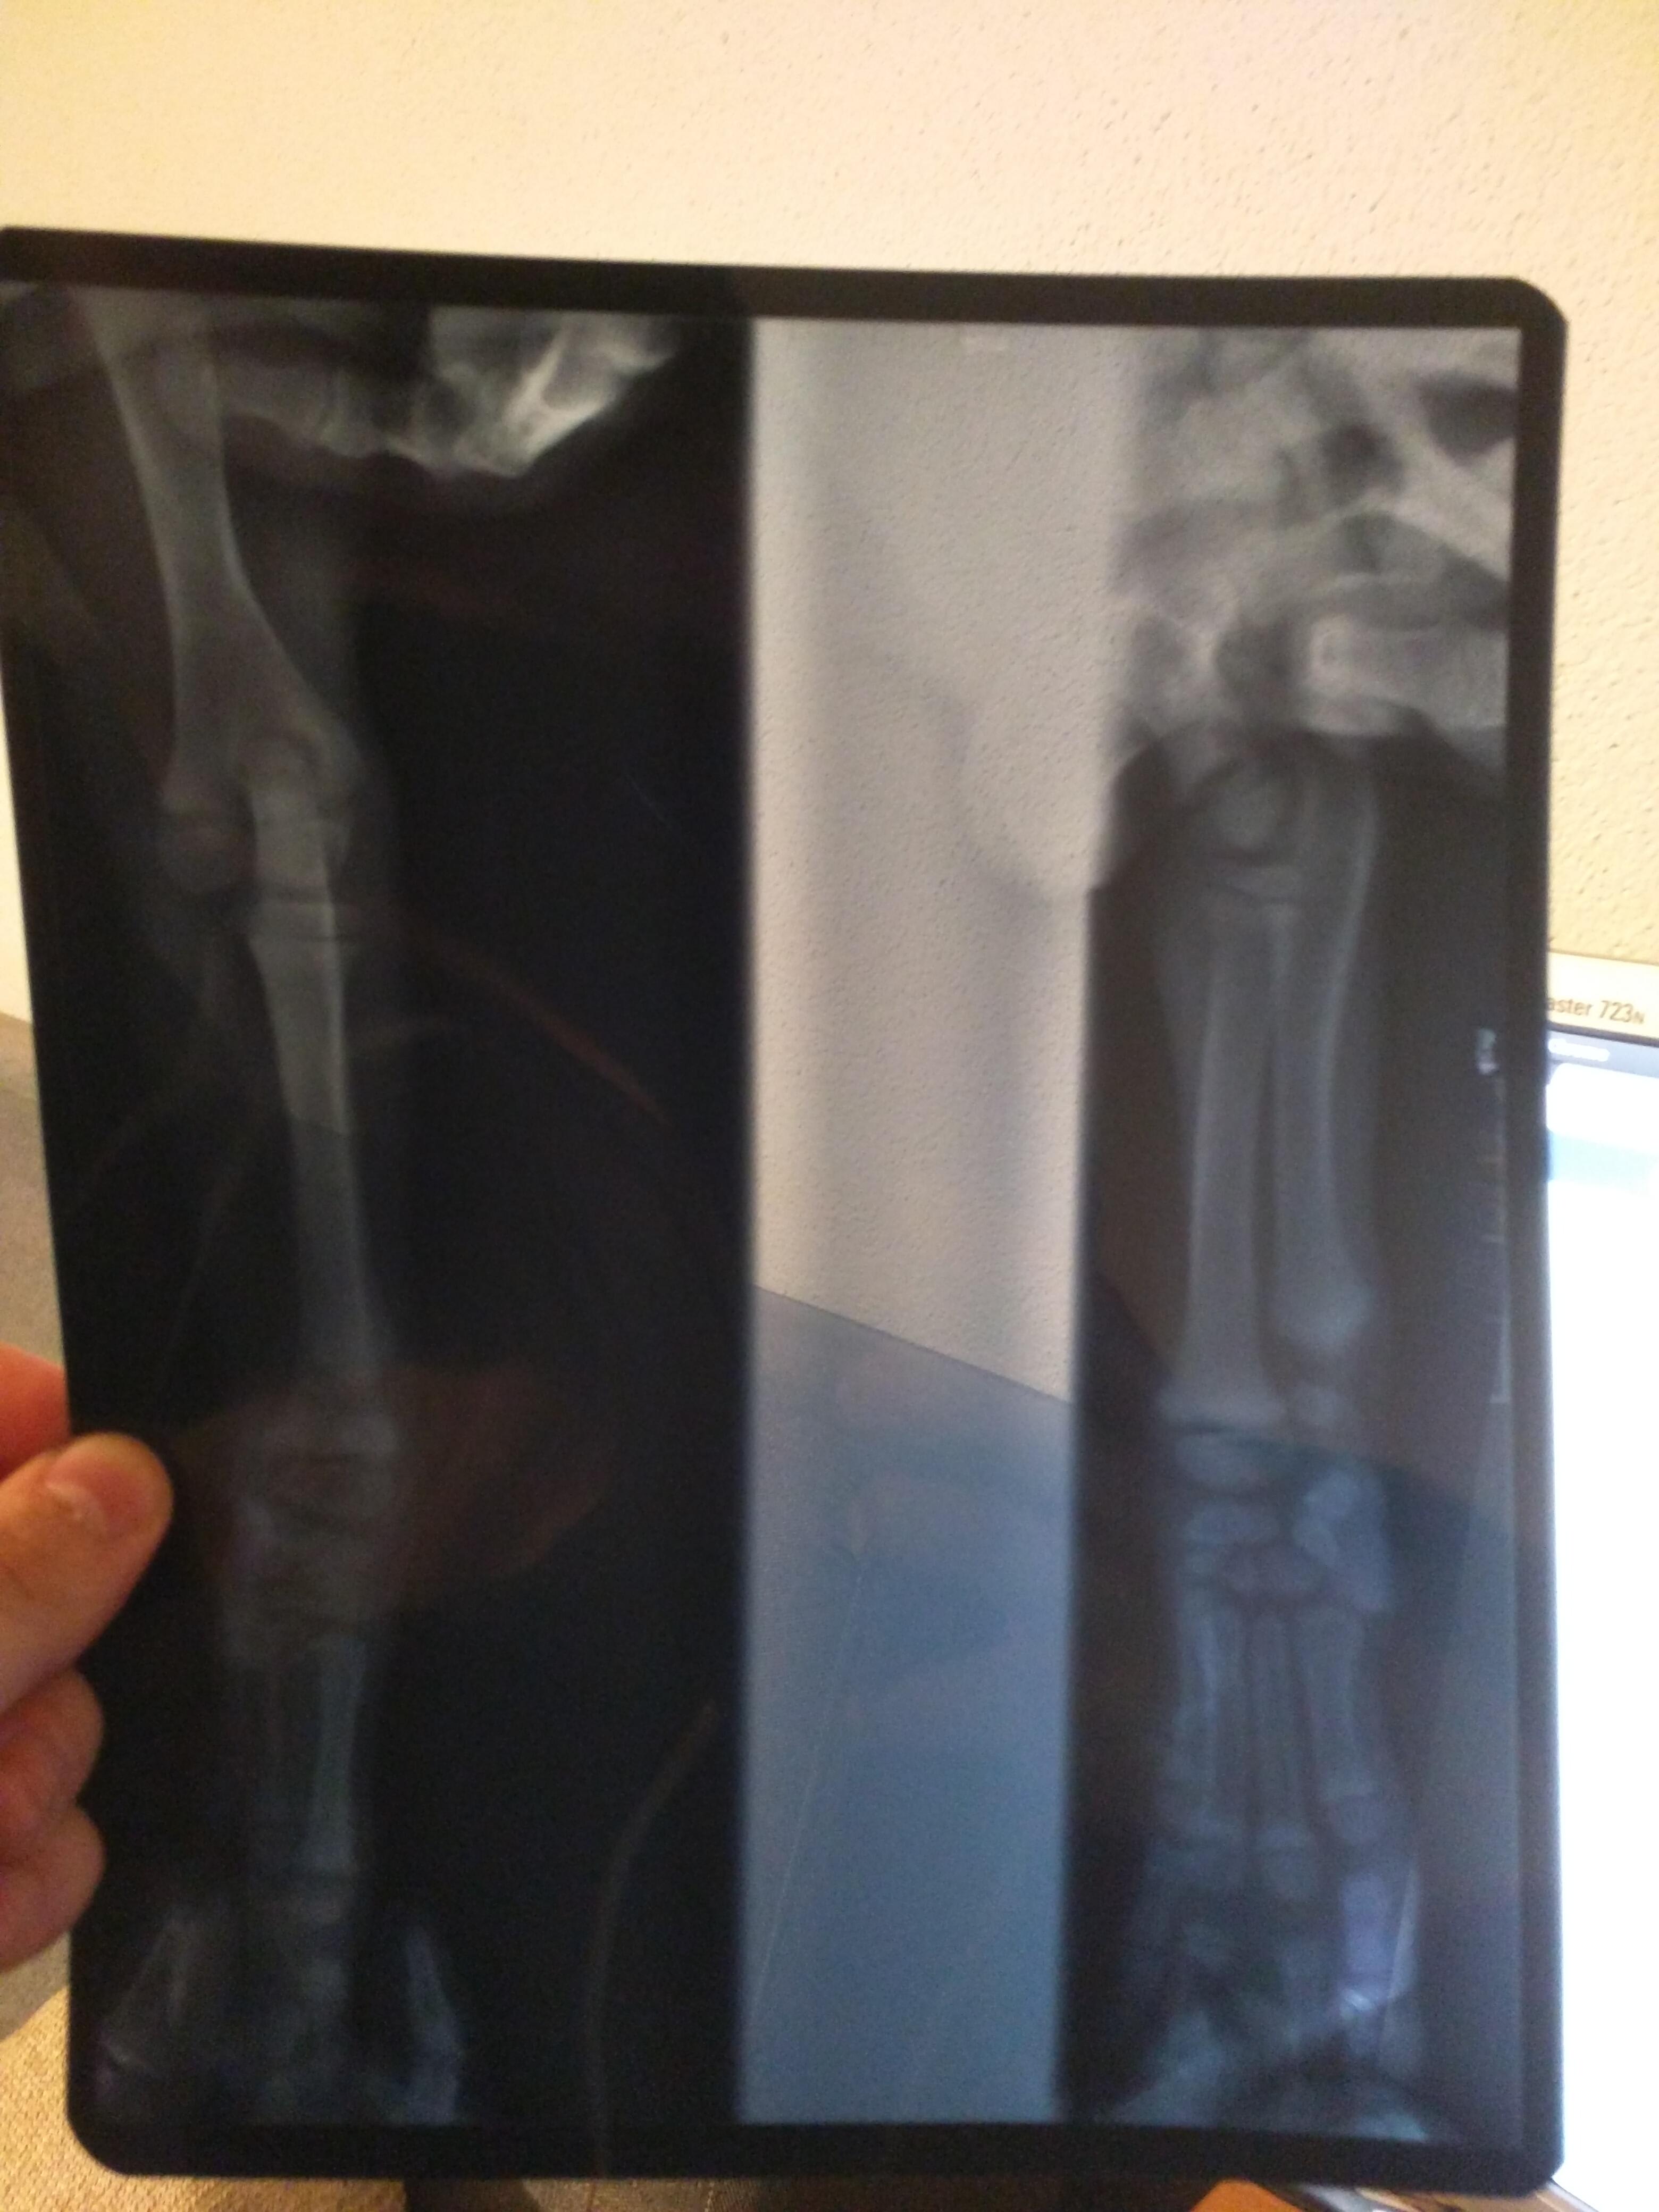

Hi, I have two month old lab puppy. He is fine otherwise, but his right (first) leg is shaking and at times his leg is bending, not standing as it should. I have done an x-ray of his leg but the specialist said that there wasn't anything odd. I can provide the scans to you, just in case. Can you help me understand what could be wrong with they puppy, and if that can be fully recovered in the future. Best regards, Ardian

Hi Ardian, I would ask your veterinarian about carpal flexural deformity. It is a condition that we can see in young puppies that have normal x-rays. They think it happens because the bones and tendons are growing at different rates, but they are not sure of the cause. The good news is that it seems to resolve in a few weeks and does not cause any long term problems. Some people recommend a diet change, but it has not been proven to make a difference. It is not recommended to splint the wrists. Good luck! I hope that was helpful. Thanks for using Petco Pet Education Center, formerly Petcoach.